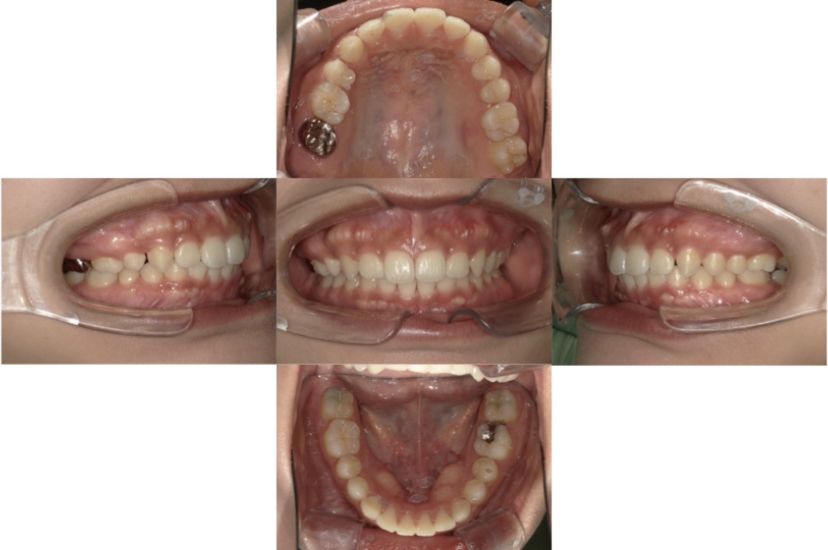

BEFORE

AFTER

上下顎叢生、反対咬合(上下の前歯のガタガタ、若干受け口)のケースです。

装置はラビアル(上下表側)で、上下顎の小臼歯を4本抜歯を行っています。抜歯したスペースを使って、上下の叢生改善と前歯の受け口の改善を行っています。

主訴 前歯のガタガタを治したい。

年齢・性別 45歳 女性

お住まいの地域 神奈川県川崎市

治療方針 抜歯スペースを利用して上前歯の叢生(ガタガタ)の改善と受け口の改善

抜歯部位 上顎左右第一小臼歯、下顎左右第二小臼歯

使用装置 ラビアル(上下表側)、顎間ゴム

治療期間 2年6か月

治療回数 20回

リテーナー クリアリテーナー